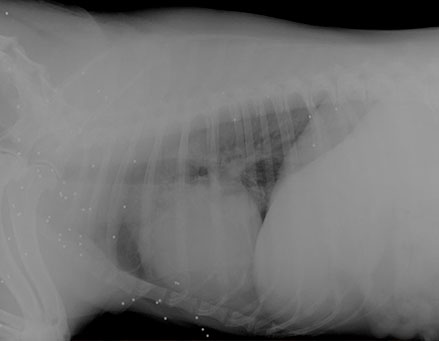

Samantha

wurde in der Türkei überfahren und auf der Straße liegen gelassen. Tierschützer nahmen sich ihrer an kümmerten sich um sie, so gut es ging. Als sie zu mir kam waren ihre Knochen bereits so schlecht zusammengewachsen, dass sie ihre Hinterbeine kaum mehr benutzen konnte. In einer Spezialklinik wurden diese nach mehrfachen Operationen Stück für Stück begradigt. Durch die schiefen Läufe sind jetzt auch ihre Hüften kaputt, die dringend weiter behandelt werden müssen.